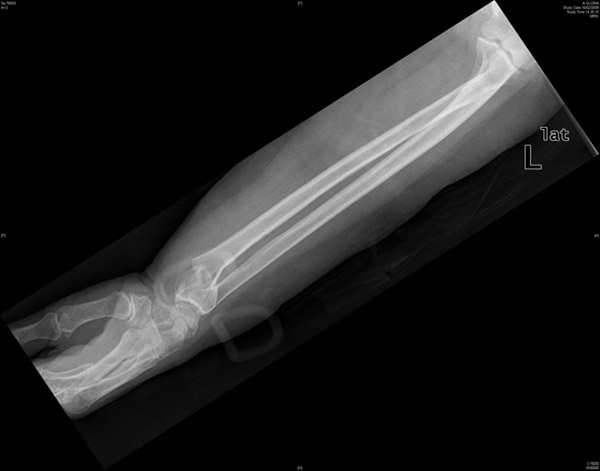

Fractura de radio.